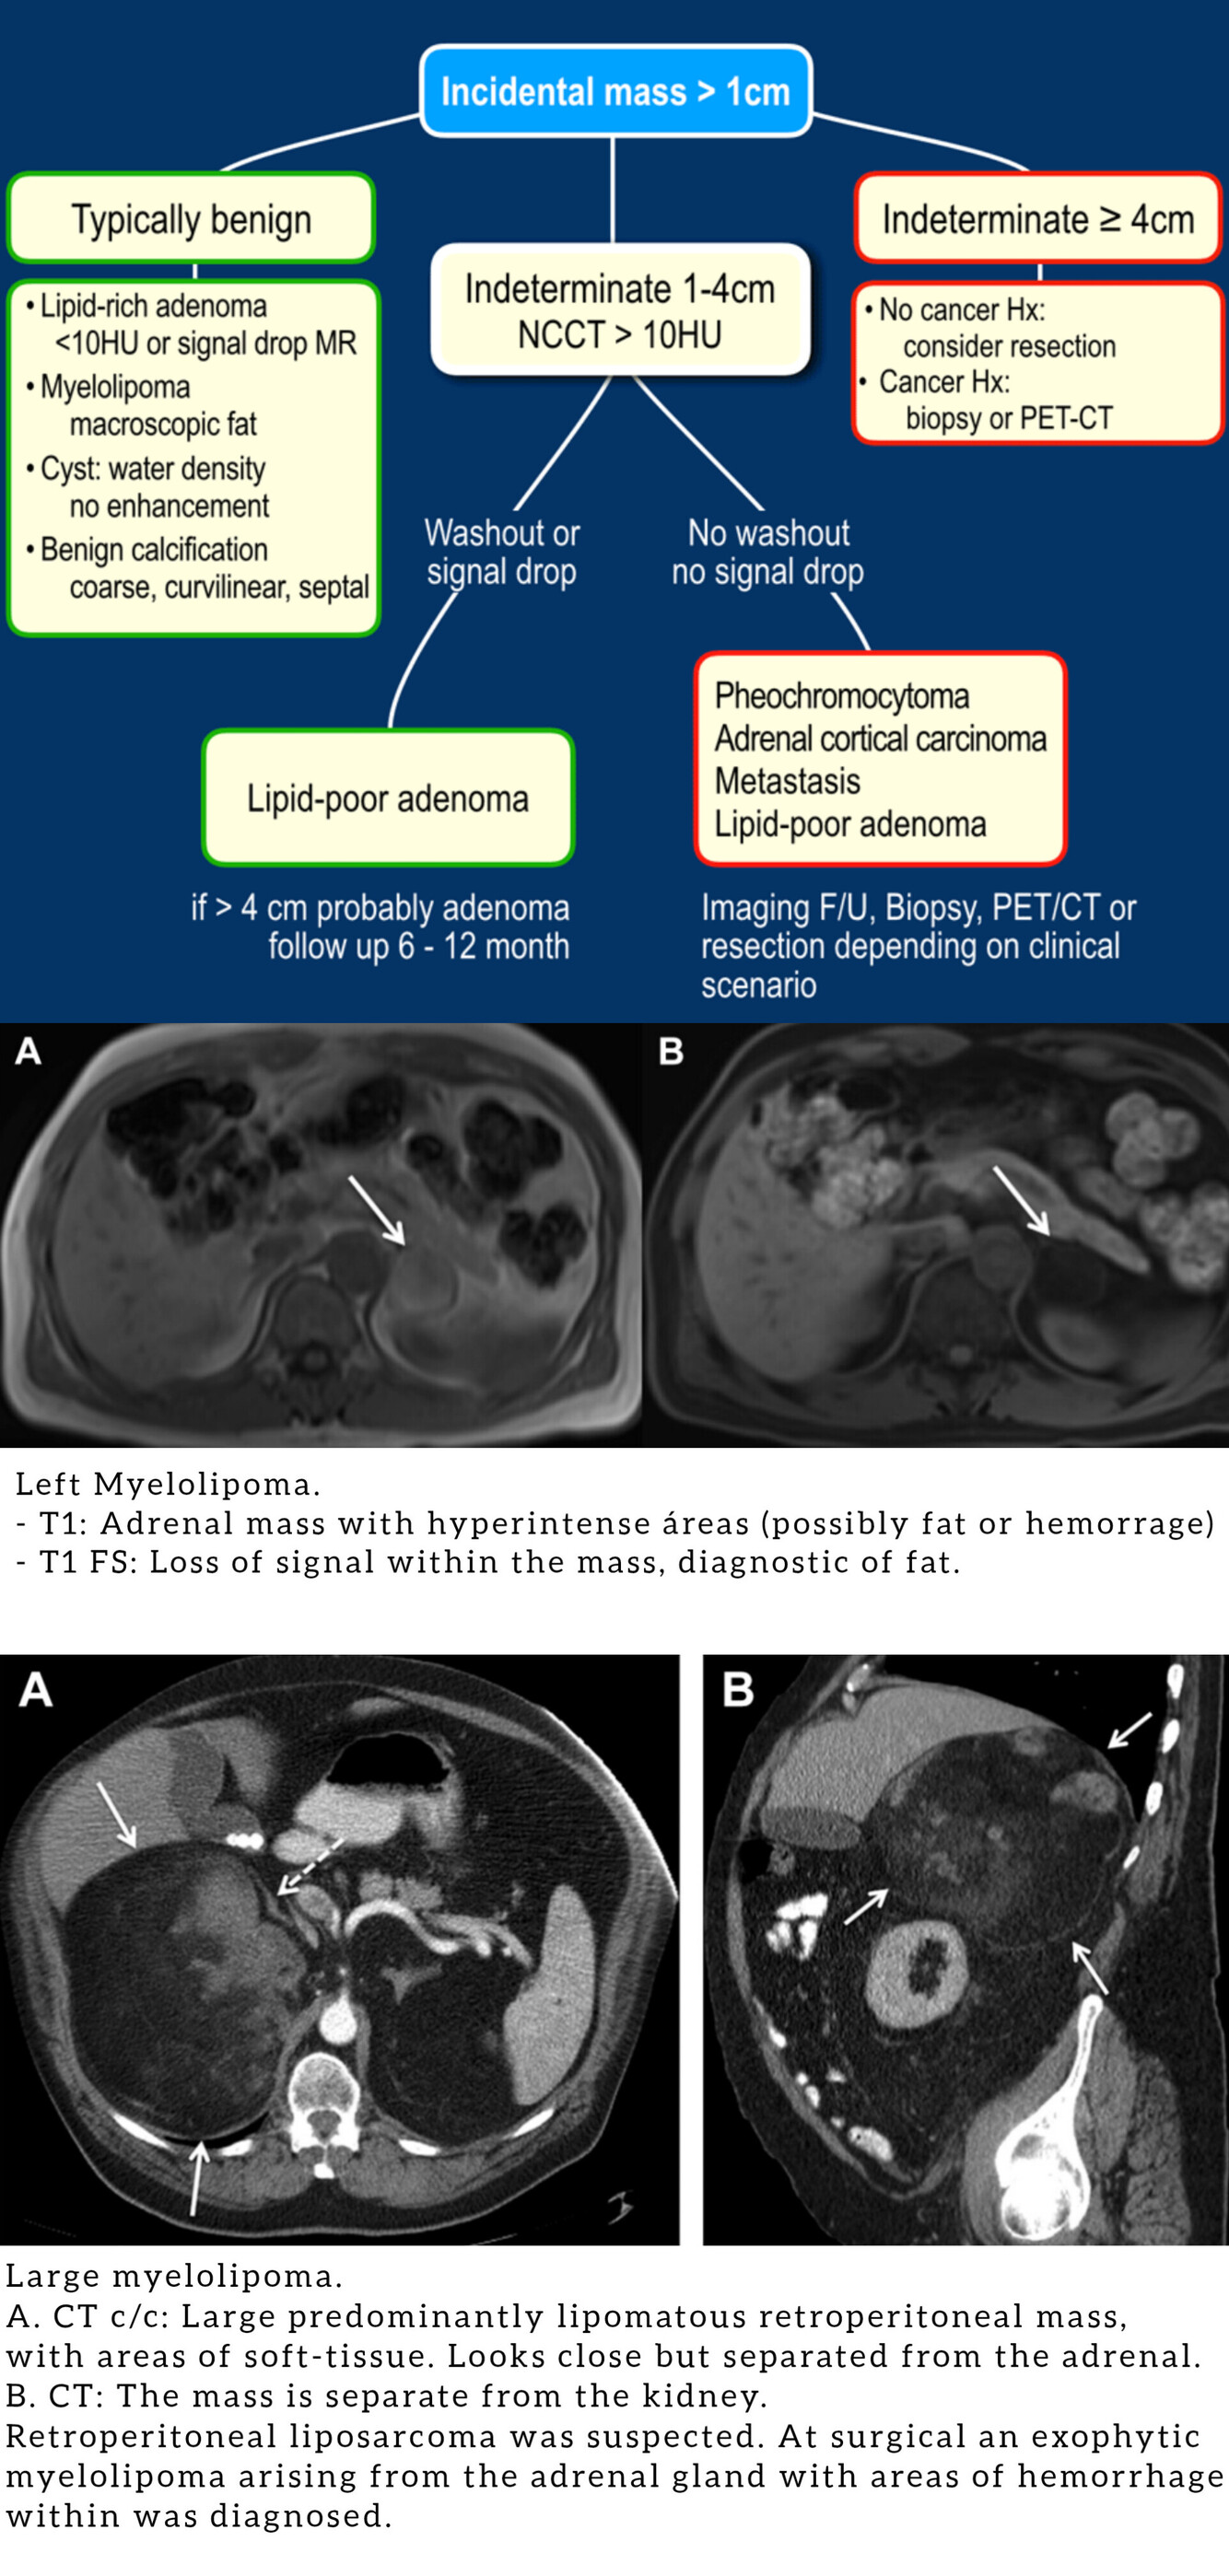

Masas Suprarrenales I

(TC a los 15 min para ver lavado).

Adenoma:

- Rico en lípidos: <10 UH o caída de señal en fuera de fase.

- Bajo en lípidos: Washout: Absoluto > 60% relativo > 40%.

Mielolipoma:

- Grasa macróscopica (no baja señal en T1 op, pero si en FS).

- DDx: Carcinoma suprarrenal, Liposarcoma, Teratoma.